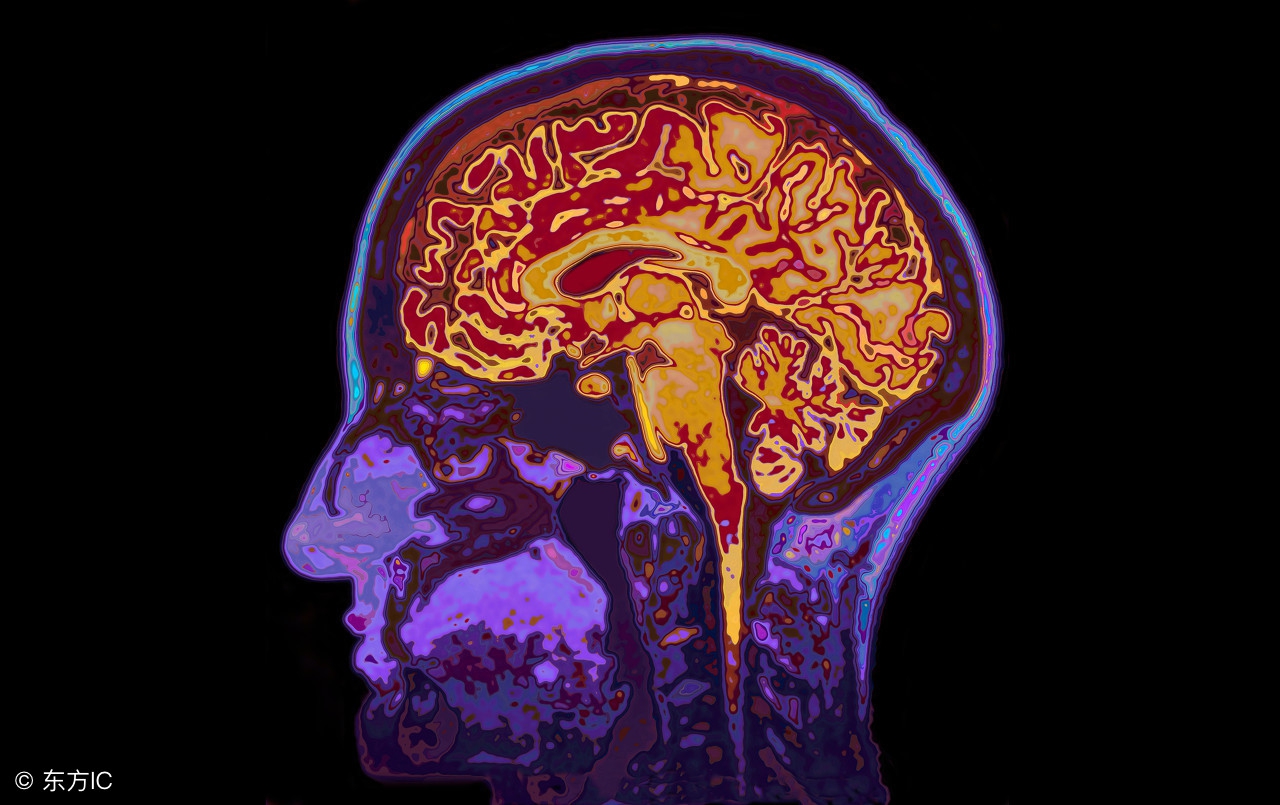

头痛的原因有许多,感冒发烧,血压异常,贫血,头部有障碍,煤气中毒,酒精中毒,便秘,神经疲劳等都会引发头胀痛。如果是身体异常导致的头部胀痛,需要及时治疗才能缓解。生活中难免会有头胀痛情况出现,不必太过紧张,科学治疗才是重点。下面就来了解一下头胀痛头晕是什么原因?

1、头部胀痛可能是因为脑膜收到了刺激,导致血管收缩能力提高,这种症状在提醒我们脑部的氧气供应不足,需要更多的氧气才能提供大脑正常生理活动。只要吸入足够的氧气到头痛的位置,这种情况就会有所缓解。比如到了高原地区,因为高原反应许多人都会出现头部胀痛情况,这是因为高原地区氧气稀薄引起的。

2、物理因素也会导致头部胀痛,颅内炎症,损伤以及肿物的压迫会导致头部血管痉挛,扩张,移位,伸展,进而刺激到大脑神经,引起头部胀痛情况。如果是这些原因引起的头部胀痛,需要及时到医院检查并治疗。